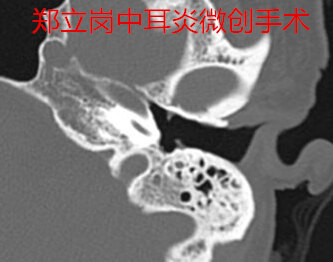

患者*党**,女,57岁,河南平顶山鲁山人。患者于1年余前无明显诱因出现左耳溢液,间断性,脓液为淡黄色、无血丝、量不多、不臭,伴左耳听力降落,逐渐减退,无明显耳痛,偶伴嗡嗡样耳鸣,伴左耳闷塞感,无伴眩晕、恶心、呕吐等症状,予以药物治疗后症状可改善,但每遇感冒、耳道进水后易再次流脓。近1月来左耳未再流脓,今门诊以"左侧慢性化脓性中耳炎"收住入院,拟进一步手术治疗。患者左侧中等大小鼓膜穿孔,手术难度不大,这次做的是全麻耳内镜中耳炎微创手术。插管全麻后就开始了手术,在耳内镜下不用做任何的体表切口,直接翻起外耳道鼓膜皮瓣。翻起皮瓣的过程中出血比较多,翻起皮瓣后取合适大小的耳屏软骨修剪后修补鼓膜,鼓膜修补好后检查了两遍确认没问题后就结束了手术。整个的手术用时约60分钟,由于出血做的非常的艰苦,但还算比较顺利。术后查房患者无明显的不适,无手术相关的并发症。